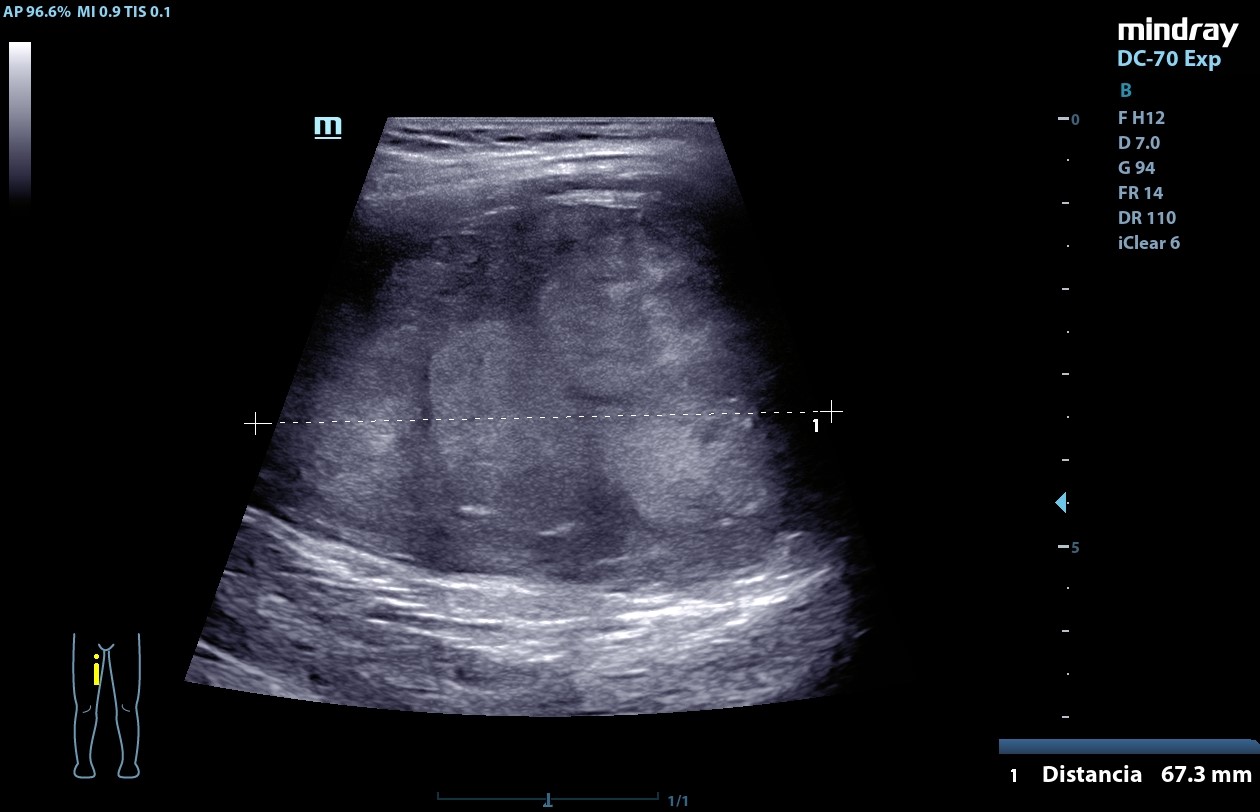

Ecografía POCUS (20/09/24): masa heterogénea de centro hiperecogénico, de bordes bien definidos, Doppler negativa de aproximadamente 52,3 mm x 37,4 mm x 67,3 mm compatible con neurofibroma plexiforme.

La ecografía es la técnica de elección para el diagnósitico de la mayoría de los tumores de partes blandas, y aunque es poco específica para el diagnóstico del neurofibroma plexiforme (habitualmente se presenta como una lesión hipoecogénica de límites bien definidos, que parecen un "tiro al blanco", como una masa fusiforme de centro hiperecogénico rodeada por tejido hipoecogénico) es importante conocerlo y saber identificarlo debido a su potencial de malignización.